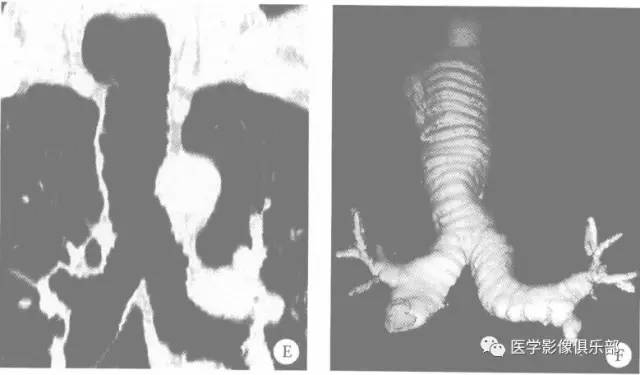

气管支气管巨大症1例X线CT

【病例】气管支气管巨大症1例X线CT